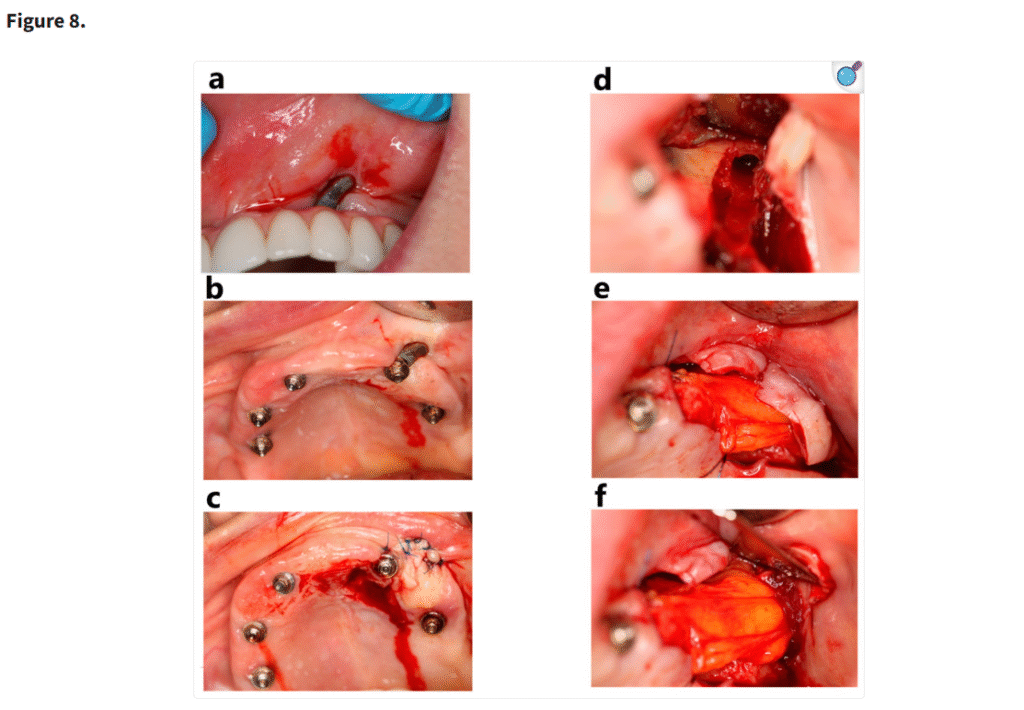

これらの写真は、上顎左側3番付近のザイゴマインプラント周囲に生じた軟組織裂開(a, b)を示している。インプラントをバーで平滑化した後、口蓋からの有茎弁で露出したインプラントを被覆しようと試みた(c)。しかし再び歯肉が露出し、上顎洞炎の再発を理由にインプラントを除去する判断となった。インプラントを除去した後(d)、生じた欠損部は頬脂肪体で被覆された(e, f)

3.1. インプラントの失敗

重度の上顎萎縮症例において、個別設計のインプラントはザイゴマインプラントと比較して低い失敗率を示した(Figure 8)。ザイゴマインプラントの生存率(96.3%)と骨膜下インプラントの生存率(97.1%)との間に統計学的に有意な差は認められなかったものの(p = 0.278)、骨膜下インプラントのわずかに高い生存率は、その患者固有の解剖学的形態に適合するカスタマイズ設計によるものと考えられる。この個別化アプローチにより、インプラントおよび周囲骨への応力集中が軽減され、安定性および長期的な統合が向上した(Figure 9)。